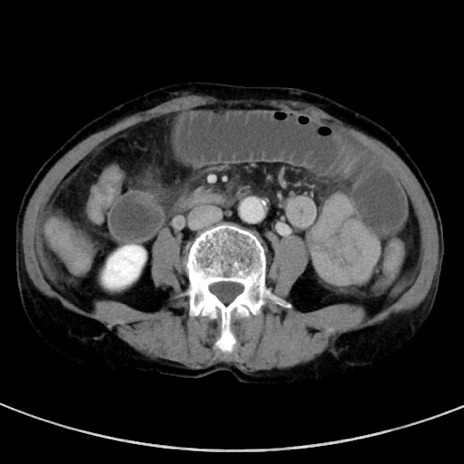

症例23(横断像)

【症例】70歳代女性

【主訴】下腹部痛・嘔吐

【現病歴】2日前より腹痛あり。昨日嘔吐あり。症状改善しないため来院。

【既往歴】胃GISTに対して胃部分切除後。

【身体所見】BT 37.1℃、BP 128/77mmHg、腹部:平坦・軟、下腹部に圧痛あり。

【データ】WBC 10200、CRP 0.31